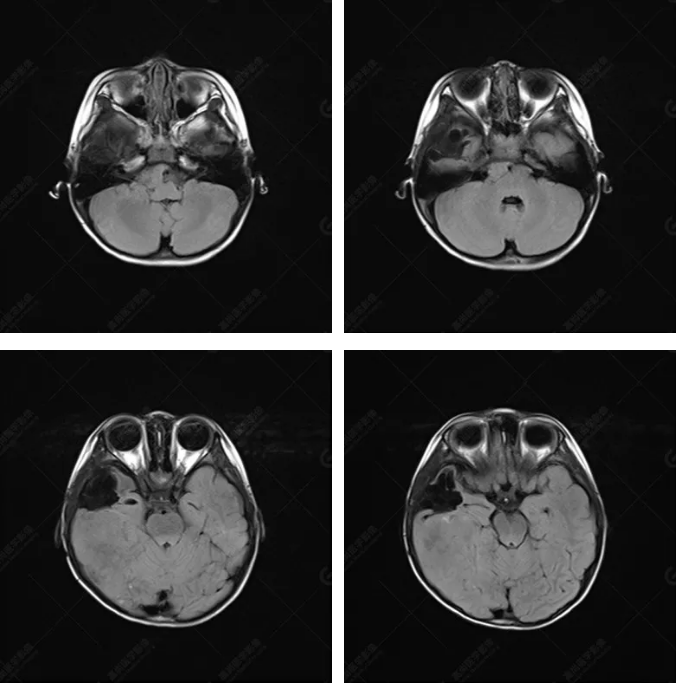

右側(cè)顳葉腫瘤切除術(shù)后(具體不詳):右側(cè)顳部骨質(zhì)不連續(xù)呈術(shù)后改變,右側(cè)顳葉術(shù)區(qū)見(jiàn)片狀長(zhǎng)T1長(zhǎng)T2信號(hào)影,F(xiàn)LAIR呈低信號(hào);術(shù)區(qū)后方右側(cè)顳枕葉見(jiàn)一巨大占位性病變影,邊界欠清,大小約6.2×5.8×4.3cm(前后×左右×上下),信號(hào)不均勻,T1WI呈等稍低信號(hào)間雜少許高信號(hào),T2WI呈高稍低混雜信號(hào),DWI示部分病灶彌散受限,相應(yīng)ADC圖減低,磁敏感序列見(jiàn)部分呈極低信號(hào),增強(qiáng)掃描可見(jiàn)明顯不均勻強(qiáng)化,鄰近硬腦膜及小腦幕增厚并明顯強(qiáng)化;另延髓右前方及右側(cè)橋小腦角區(qū)見(jiàn)一不規(guī)則形異常信號(hào)影,大小約3.2×1.3×3.7cm(左右×前后×上下),呈長(zhǎng)T1稍長(zhǎng)T2信號(hào),F(xiàn)LAIR呈等信號(hào),DWI未見(jiàn)受限,增強(qiáng)后明顯均勻強(qiáng)化,鄰近腦膜明顯強(qiáng)化。鄰近腦實(shí)質(zhì)及右側(cè)顳角明顯受壓;左側(cè)大腦半球未見(jiàn)局灶性信號(hào)異常,中線結(jié)構(gòu)稍左移。

右側(cè)顳葉腫瘤切除術(shù)后:現(xiàn)術(shù)區(qū)后方右側(cè)顳枕葉及延髓右前方占位,右側(cè)顳枕部硬腦膜及小腦幕明顯強(qiáng)化,結(jié)合既往影像資料,考慮為胚胎源性惡性腫瘤,如非典型畸胎樣/橫紋肌樣瘤(AT/RT)或原始神經(jīng)外胚層腫瘤(PNET)。

非典型畸胎樣/橫紋肌樣瘤(AT/RT) 是一種高度惡性中樞神經(jīng)系統(tǒng)腫瘤,臨床罕見(jiàn),臨床表現(xiàn)無(wú)特異性,好發(fā)于 5 歲以下兒童,尤以 3 歲以下多見(jiàn),在兒童原發(fā)性中樞神經(jīng)系統(tǒng)(CNS)腫瘤中占 1%~3%。該腫瘤體積一般較大,幕上大于幕下,有明顯的占位效應(yīng)。該腫瘤成分復(fù)雜,囊變、出血、壞死常見(jiàn)。因此 AT/RT信號(hào)混雜,囊性部分呈 T1WI低、T2WI高信號(hào),增強(qiáng)后不強(qiáng)化;若瘤體出血,囊內(nèi)可見(jiàn)T1WI稍高信號(hào)、T2WI低信號(hào),實(shí)性部分在 T1WI上呈混雜等、低信號(hào),在T2WI 及 T2-FLAIR上呈混雜等高信號(hào),增強(qiáng)掃描后大部分呈環(huán)形條帶樣明顯強(qiáng)化,中心壞死區(qū)不強(qiáng)化。另外,該腫瘤實(shí)性成分在DWI上呈高信號(hào),說(shuō)明腫瘤細(xì)胞核密集,水分子擴(kuò)散明顯受限,提示該腫瘤惡性程度高,容易復(fù)發(fā)及轉(zhuǎn)移。